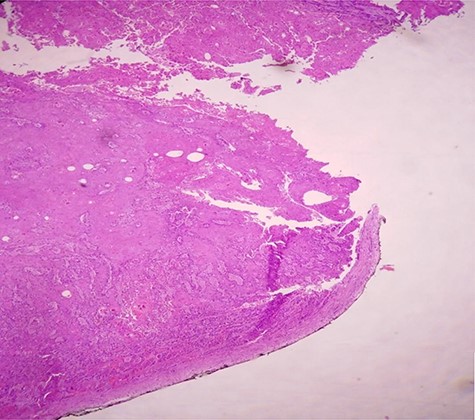

H & E staining viewed under x40 with Olympus CX23 showing a well differentiated SCC (Presence of keratin pearls and intercellular bridges).